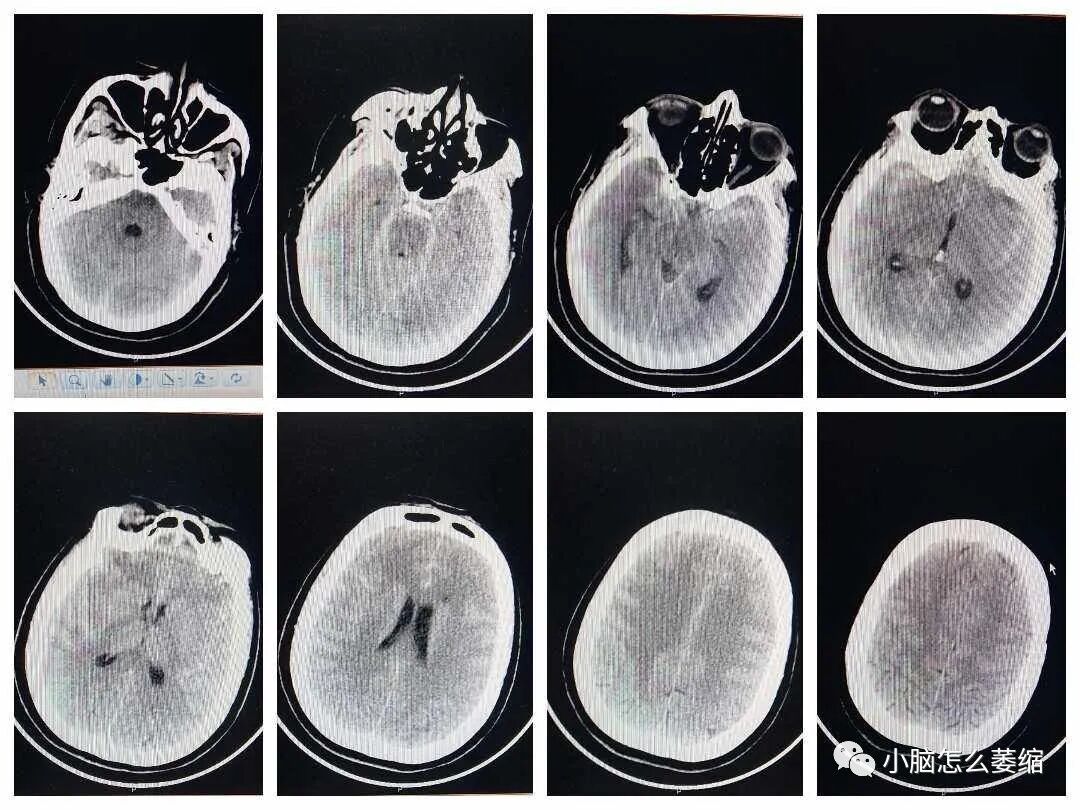

小脑萎缩是一种较为常见的神经系统疾病,患者常常出现平衡障碍、运动障碍以及语言障碍等症状。近年来,越来越多的研究关注中药在治疗小脑萎缩方面的应用。本文将介绍一例小脑萎缩患者接受中药治疗的案例,以期为小脑萎缩的治疗提供新的思路和方法。

患者张女士,今年68岁,退休教师。三年前,她开始出现明显的平衡障碍,步态不稳,且语言表达逐渐变得含糊不清。在某三甲医院确诊为小脑萎缩后,张女士开始了漫长的治疗旅程。她曾接受过西医药治疗,但副作用明显,让她苦不堪言。经过朋友推荐,张女士的治盛劲强大夫治疗小脑萎缩的效果不错,于是预约了盛大夫的面诊号位。盛大夫中医辨证为“痿证”采用补髓健脑汤加减药物治疗。